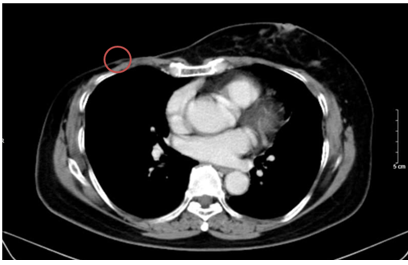

+ Phổi phải: nhu mô thuỳ giữa và dưới có các khối – nốt đặc, lớn nhất 19x18mm

+ Phổi trái: nhu mô thuỳ trên và đáy phổi sát màng phổi có các khối nốt đặc, lớn nhất 16x17mm

Hình 2. Hình ảnh chụp CT ngực trước điều trị: Tổn thương phổi 2 bên